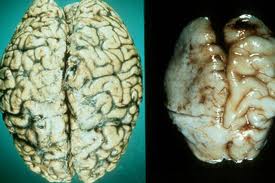

Мозг в норме(справа), мозг при алкогольной энцефалопатии (слева)